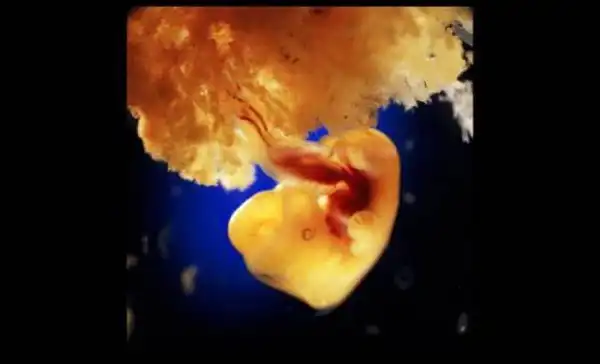

22 день развития эмбриона. Серое вещество — это будущий головной мозг

На 18-й день у зародыша начинает пульсировать сердце

28-й день после оплодотворения

40 дней. Наружные клетки зародыша срослись с рыхлой поверхностью матки и образуют плаценту